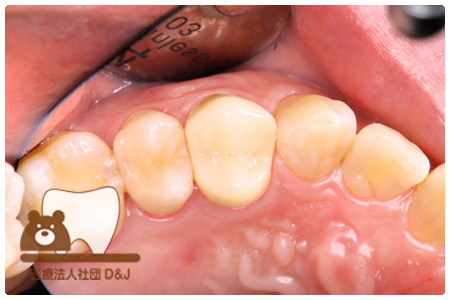

症例4フルジルコニアクラウン 左下6

治療前

治療後

37歳 男性

- 治療内容

- 以前のクラウンがセメントの劣化により外れた為その上にフルジルコニア製の被せ物を装着しました。見た目と強度を両立した自由診療の治療です。

- 治療期間

- 1カ月

- 費用

- 自費

フルジルコニアクラウン:77,000円(税込)

(R8.1月時点)

- その他の治療の費用は含まれておりません。

- リスク・副作用

- 硬い素材のため、かみ合う歯に負担がかかることがあります。将来取り外す場合に歯に負担がかかることがあります。強い力が加わると、まれに欠けたり割れたりすることがあります。